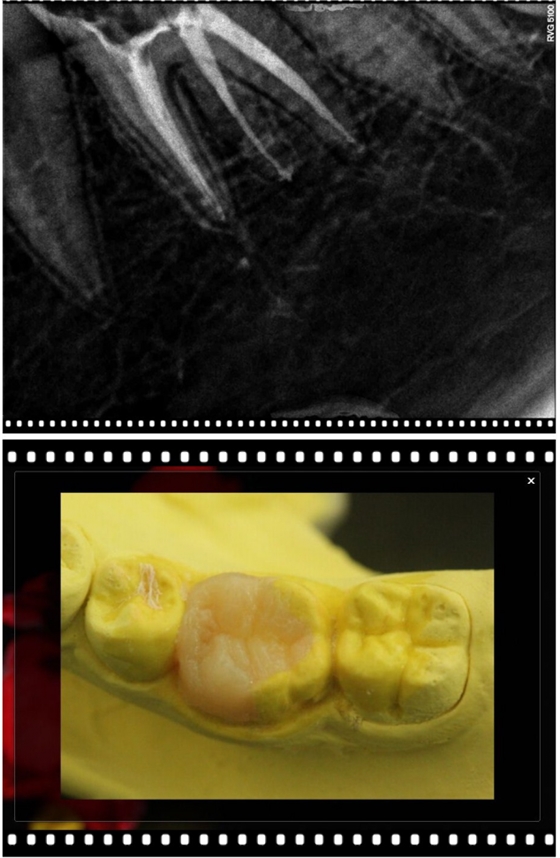

以下病例大部分是以Kerr的低端Neofil通用樹(shù)脂修復(fù)(基本都是粗拋紅標(biāo)車針),修復(fù)調(diào)合后即刻照。